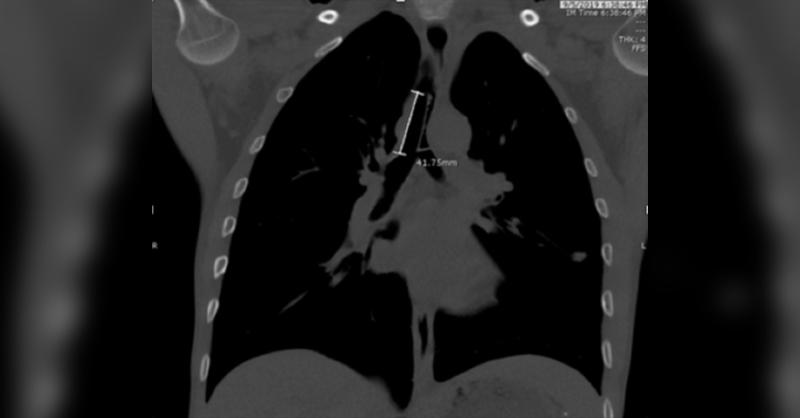

A 34-year-old man who is on tracheostomy presented with shortness of breath and self-reported foreign body aspiration. He had been tracheostomy dependent for several years due to bilateral vocal cord immobility and subglottic stenosis due to prior trauma. He stated that when he coughed, the Montgomery cannula "slipped into his throat." He went to t